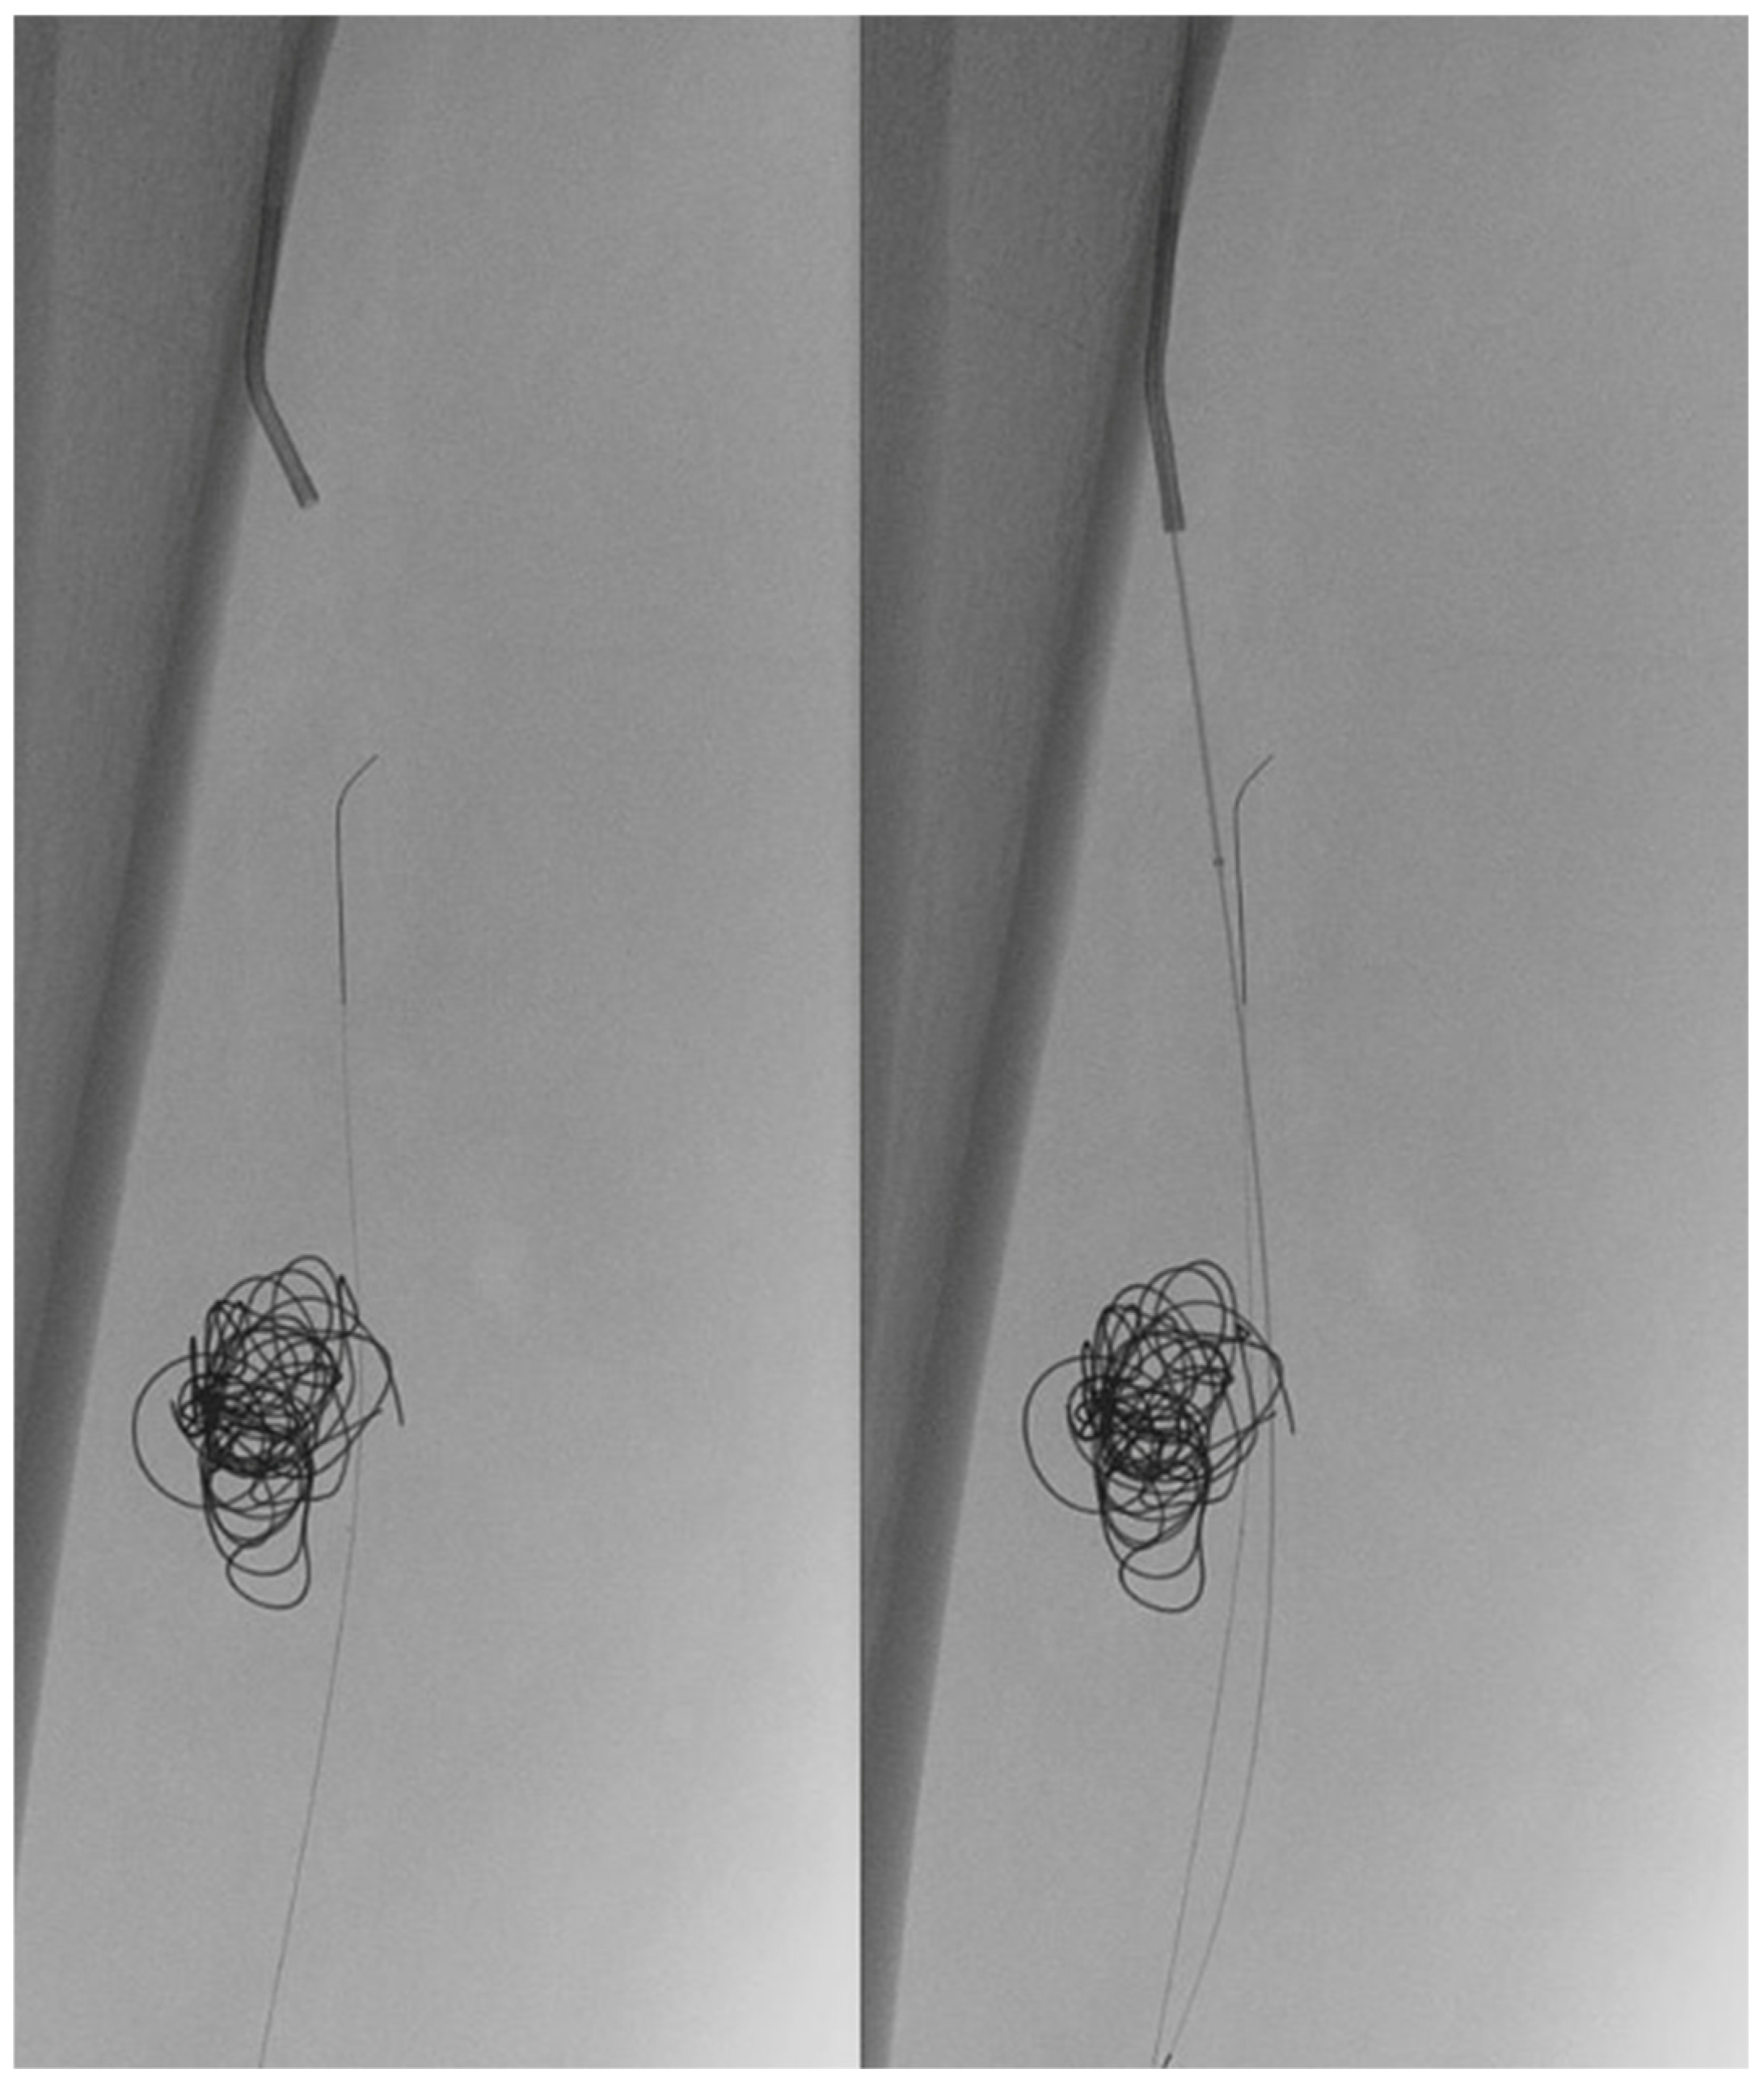

In light of a symptomatic aneurysm, treatment was offered to the patient. After discussing the risks of open and endovascular treatment options with the patient, an endovascular approach was opted for. The presence of a large aneurysm with an AV fistula and venous congestion posed an increased risk of significant bleeding complications associated with open surgery. An antegrade femoral access was obtained via a 5F sheath (Terumo, Shibuya-ku, Tokyo, Japan). After obtaining an angiogram, two coils were deployed in the aneurysm sac (Concerto PGLA helical PV-20-50-Helix and Concerto PGLA 3D PV-18-40-3D, Medtronic, Minneapolis, MN, USA), with the aim of causing sac thrombosis and obliterating the flows from multiple AV fistulas. As anticipated, this did not lead to complete occlusion of the aneurysm and AV fistula. A retrograde pedal access was obtained, and cannulation of the PTA was successfully performed with a V14 guidewire (Boston Scientific, Marlborough, MA, USA) (Figure 2 and Figure 3). After obtaining guidewire access, the aneurysm was excluded with a stent graft (Viabahn Endoprosthesis 5 mm × 50 mm, WL Gore, Flagstaff, AZ, USA). Immediately after the procedure, angiography control visualized complete exclusion of the pseudoaneurysm, occlusion of the sac, and absence of any AVF (Figure 4). Postoperatively, the patient reported pain reduction. Both pedal pulses were palpable. Postoperative antithrombotic therapy included aspirin 100 mg and clopidogrel 75 mg daily for 6 months. Additionally, Class 2 compression stockings were recommended for 1 month. After 18 months of follow-up, the patient was free of symptoms, and the stent graft was patent.

Figure 4.

(Left) to (right). Coils and Viabahn stent graft. Post-stenting angiogram showing excluded aneurysm and fully deployed Viabahn.